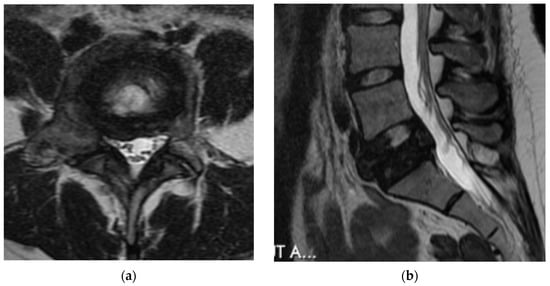

4.2.5. MRI